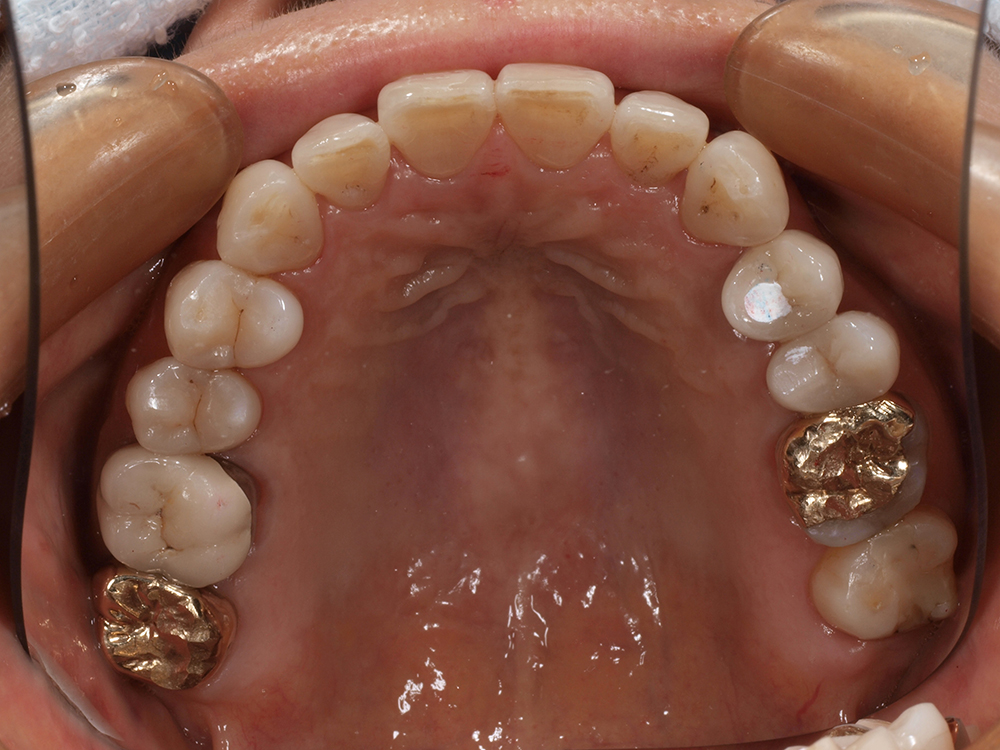

53歳 男性

- 主訴

- 全然噛めない。上の歯が取れてきた

- 処置内容

- 上顎:8本 下顎:2本

- 治療費用

- 上顎:約320万円(税込)、下顎:約160万円(税込)

- 治療期間

-

上顎:1年(仮歯まで8か月)

下顎:8か月(仮歯まで5か月)

- リスク

- 上部構造物、仮歯の破折、術後の腫れ(3日)、人工歯根脱落リスクがあります